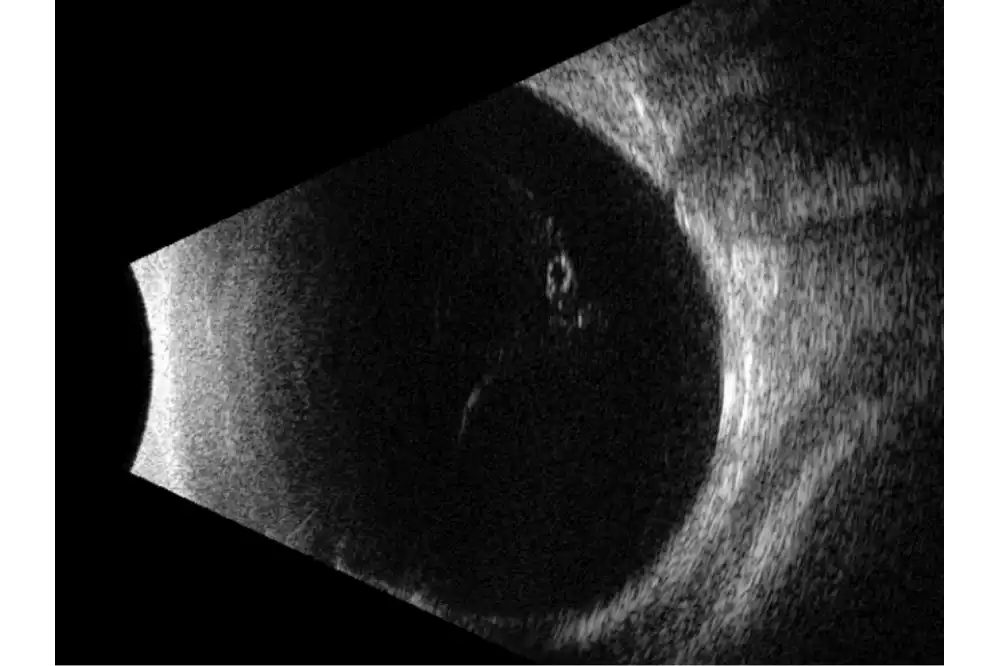

Quantel Medical heeft een sprong voorwaarts gemaakt met de nieuwe technologie met 5 ringen op een 20 MHz-sonde. Het principe is om om en om ultrasone geluidsgolven uit te zenden via 5 concentrische transducers in dezelfde sonde. Deze technologie:

- Verhoogt het focusgebied

- Vermindert de laterale resolutie van 250 naar 200 µm, oftewel met 25%

- Behoudt een hoge axiale resolutie

Het volledige oog is nu zichtbaar met een uitstekend detailniveau.

Belangrijke kenmerken

- Verhoogde scherptediepte waardoor het gehele oog zichtbaar is.

- Hoge resolutie die het mogelijk maakt om van het voorste gedeelte van het glasvocht tot aan de wand te zien.